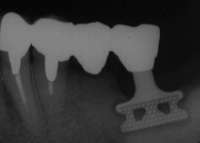

3│は歯根破折のため保存不能、抜歯とともにHAP補填。「345Fop+HAPの上 「6部にブレードタイプ、65」部にポーラスタイプ(HAPコーティング)インプラント (いずれも京セラ)植立。ED43A@│@Br、「3456連結冠装着。

遠隔地からの来院でもあり、1年に1回程度のメインテナンス継続中。経過良好。

ポーラスタイプの数少ない成功例に1つである。失敗例は後日掲載を予定しているが ポーラスタイプの善し悪しを論ずるのではなく、そこに現れた現象を医学的な観点から 考察し歯科医学の発展に貢献したいと思う。

セルフスタンディングも可能とのふれ込みで発売されたポーラスタイプ故に、新たな 可能性を求めて行った過渡期の症例である。 ともあれ、今から考えると無謀とも思われる設計にも関わらず10年間何らトラブルを 生じることなく快適に経過した本症例は、患者の絶大な賞賛の下今後更に10年近く機能する ものと思われる。しかし、本症例成功の秘密は、患者自身の免疫力の強さに大きく依存 していることを強調したい。

ポーラスタイプもたまには、強固な維持と親和性を発揮するんだなーと感心しました。